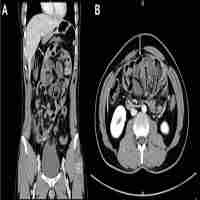

An incidental intra-operative finding of sclerosing encapsulating peritonitis, "abdominal cocoon" in an emergency presentation of small bowel obstruction, a case report.

| Subject Keyword | Sclerosing encapsulating peritonitis Abdominal cocoon Case report |